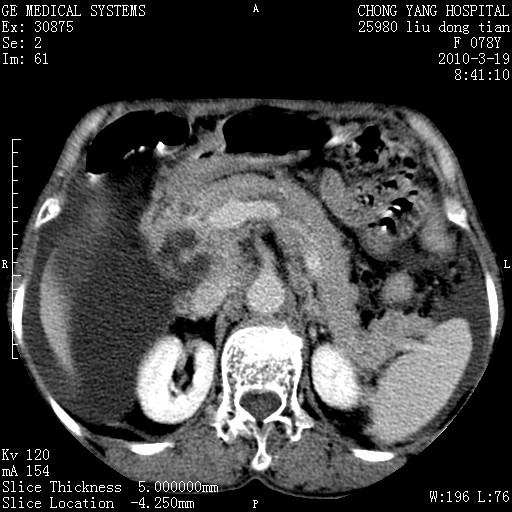

标题: CT25199:F 78Y 腹胀半年 消瘦乏力 [打印本页]

考虑nhl,肝、脾、腹膜腔及腹膜后多发淋巴结受侵,腹水,右肾囊肿,慢性胆囊炎,右侧少量胸腔积液。

分开来讲:肝左叶、尾叶病灶有不均强化像肝癌;

肝门、胰腺头、腹膜后多个团块: 淋巴瘤,转移;

胰头有肿块形成,胰头ca伴肝脾、腹膜腹膜后转移

胰头ca伴肝脾、腹膜腹膜后转移!

最后报的胰头癌多发转移,脾脏单独考虑囊肿或淋巴管瘤。